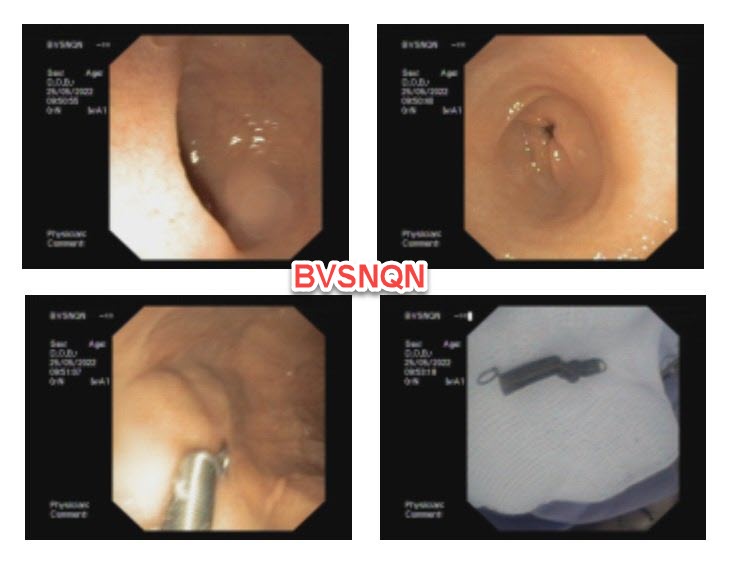

Kết quả chụp X-quang cho thấy hình ảnh dị vật cản quang ngang mức đốt sống L1. Qua hội chẩn chuyên khoa, các bác sĩ quyết định Chỉ định nội soi tiêu hóa cấp cứu gắp dị vật cho bệnh nhi. Kết quả nội soi ghi nhận di vật hình lò xo kim loại, kích thước 3x1cm tại vị trí tá tràng đã được gắp ra an toàn

Với tính chất có đầu sắc nhọn và xoắn của dị vật, nếu không kịp loại bỏ sớm dị vật rất dễ móc, mắc lại gây rách, thủng niêm mạc tại các vị trí dị vật đi qua